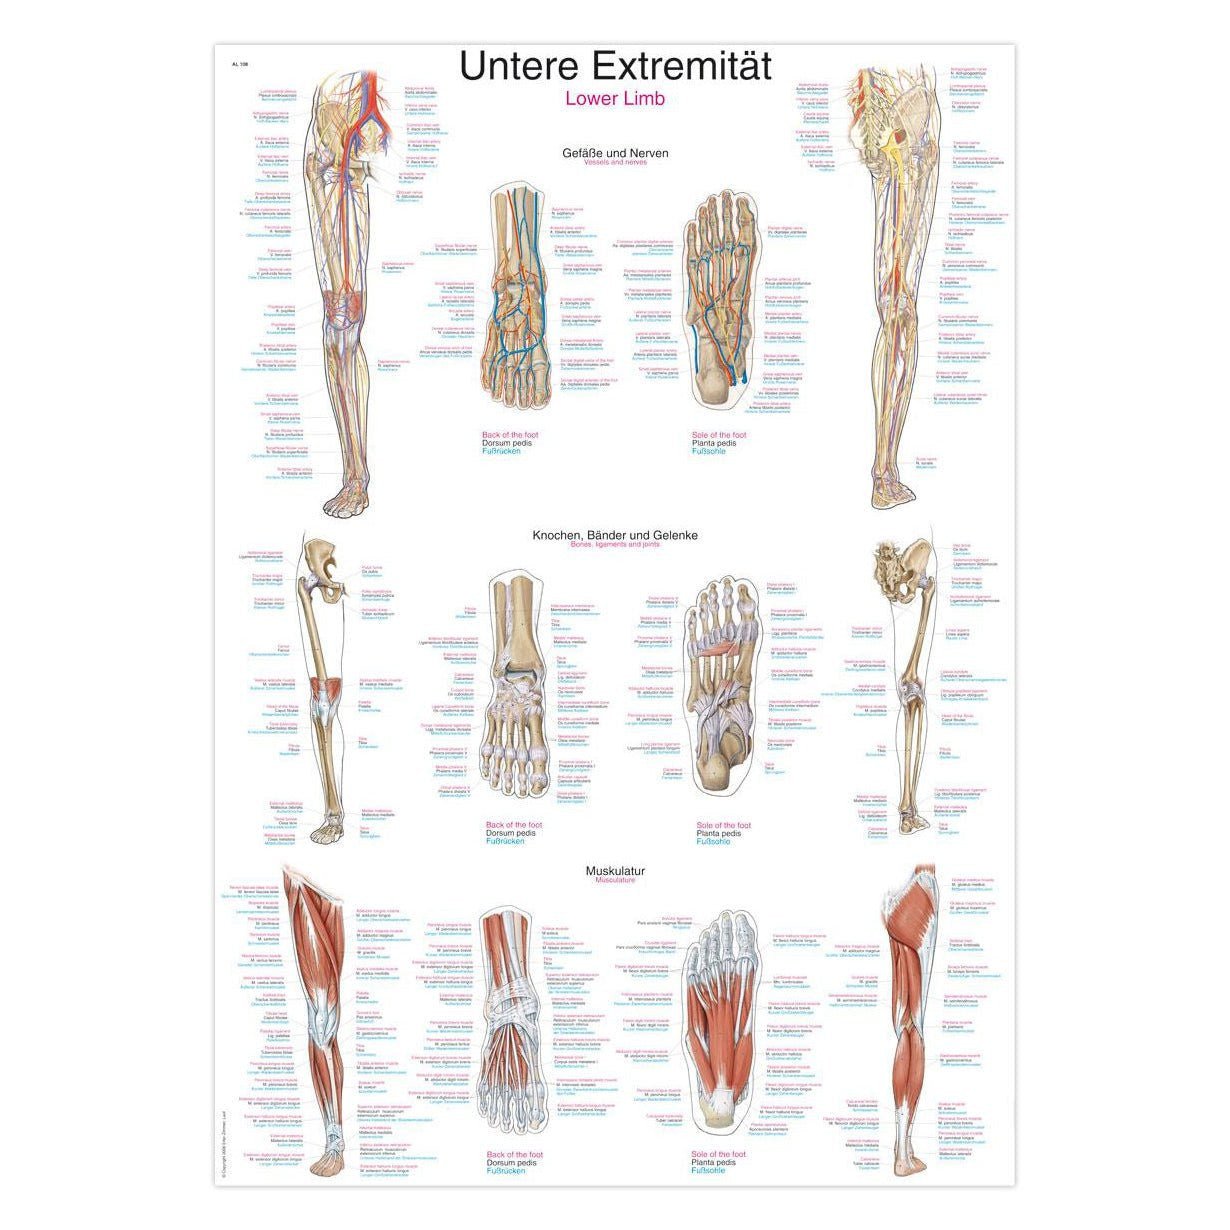

Muscle posters

Muscles provide movement to the musculoskeletal system, and their origins, insertions and lodges are clinically important for every healthcare professional. That is why we at eAnatomi have both developed and designed our own anatomy posters, which provide the ultimate overview of all the muscles of the body. On this page you can find both our own posters and posters from other manufacturers. We offer posters in several different languages such as pure Latin, Danish, English and Swedish, etc.